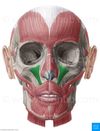

Cranial Nerve VII (Facial Nerve)

PATH: cellbodies originate in pons and medulla–>through internal acoustic meatus and facial canal–> exits stylomastoid foramen

RESPONSIBILITIES:

- Motor supply to the muscles of facial expression

- (Bell’s Palsy-paralysis of muscles of facial expression; no apparent etiology/idiopathic; suspect edema 2’ infection)

- Motor: stylohyoid and posterior belly of digastric ms.

- Parasympathetic innervation (motor): secretion of tears (lacrimal gland) and saliva (sublingual and submandibular salivary glands)

- Special sensory: taste to anterior 2/3 of tongue and palate

To Zanzibar By Motor Car

- temporal

- zygomatic

- buccal

- mandibular

- cervical

*Most frequently paralyzed cranial nerve containing motor fibers*